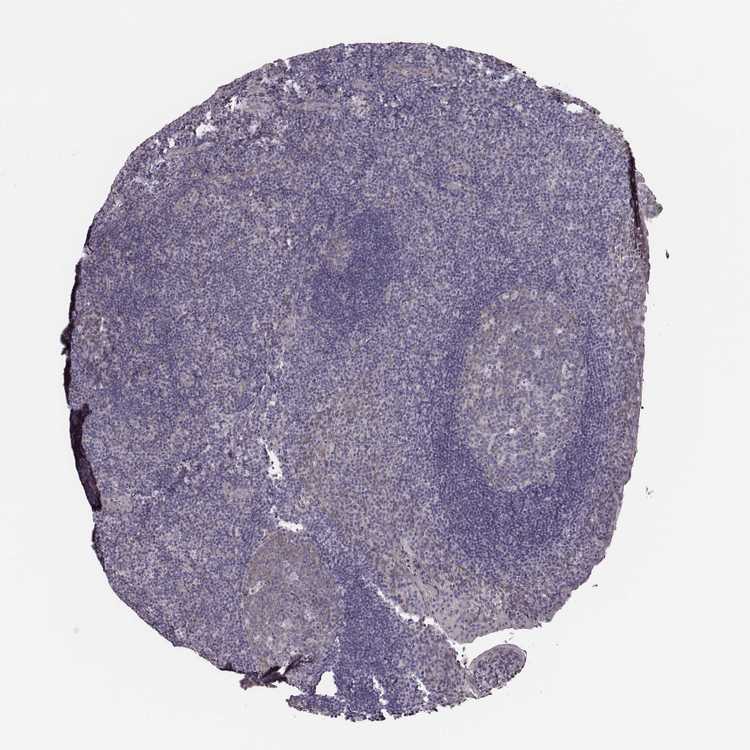

KAAG1